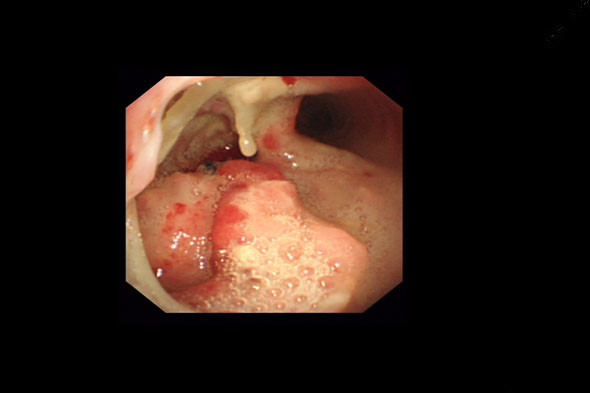

患者,男性,56岁,是一名食道癌晚期并发食管气管瘘患者,入院时已多日没进食,极度消瘦。医生给予患者行支气管镜检查后,明确瘘口直径达4cm,伴肿瘤组织侵犯气管。为挽救病人生命、提高患者生存质量,医生团队经过认真研究,制定了目前最有效的治疗方案——气管覆膜支架植入封堵瘘口。主任的一句“我们共同努力!”给患者传递了必胜的信心。

支架前